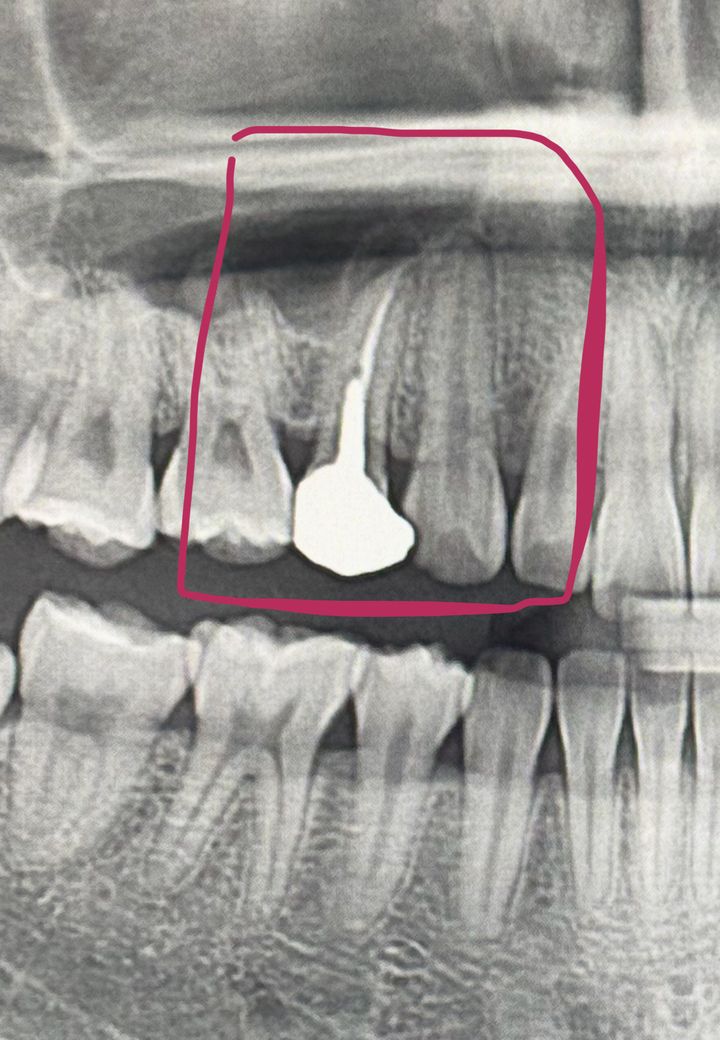

깊은 기둥을 박은 5년전 신경치료 치아에 뿌리 염증이 생겨 치료가 필요해보이는데,

깊은 기둥을 박고 치아가 얇아서 재신경치료가 어려울 수도 있지만 정 치아를 살리고 싶으면 치근단 절제술이라도 해야 한다고 말을 들었는데...

아무래도 해당 치아의 뿌리 끝 부근이 상악동이라고 하는 공기 주머니에 너무 인접해서 치근단절제술 보다는 재신경치료를 하시는 편이 좋아보이지만 post(말씀해주신 기둥)도 있고 치아도 얇기 때문에 혹시 재신경치료를 위해서 post와 크라운을 제거하는 과정에서 치아가 부러질수도 있기 때문에 해당 내용은 충분히 알고 계시는게 좋겠습니다.

(질문에 대한 답변으로. 1) 사진상으로는 치아 파절 가능성이 있긴 하지만 재신경치료 가능해보입니다. 2) 아무래도 대학병원에서는 충분한 장비도 구비해두고 일반 의원 보다는 더 많이 어려운 진료를 보는 경우가 다수 있기 때문에 조금 더 신뢰할 수 있지만 예약이 조금 밀릴 수 있다 라고 생각하시면 됩니다.)

기둥을 세운 치아의 경우 치근단칠환이 생겼다는것은 치근에 금이 갔을 가능성이 있습니다.

치아의 뿌리에 금이 갔다면 치아를 발치해야 할수도 있습니다.